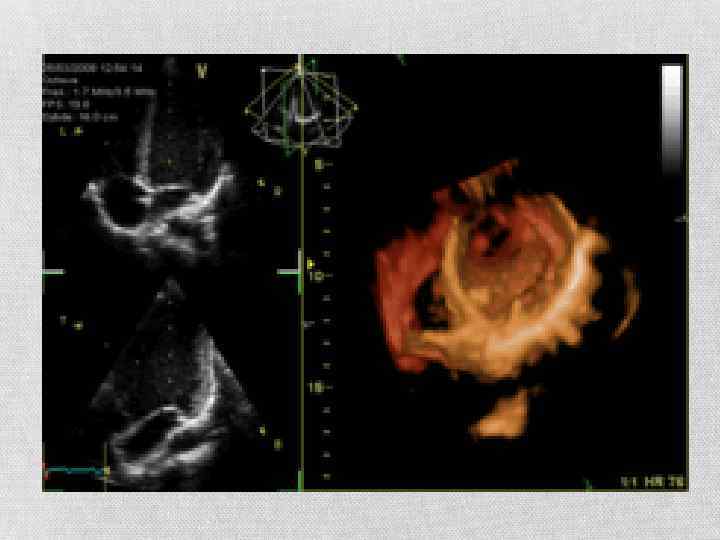

Кардиология, сосудистая кардиохирургия. Эхокардиография (Эхо. КГ) — это ультразвуковая диагностика заболеваний сердца. В этом исследовании оцениваются размеры сердца и его отдельных структур (желудочки, предсердия, межжелудочковая перегородка, толщина миокарда желудочков, предсердий и т. д. ), наличие и объем жидкости в перикарде — «сердечной сорочке» , состояние клапанов сердца. С помощью специальных расчетов и измерений Эхокардиография позволяет определить массу сердца, сократительную способность сердца — фракцию выброса и т. д. Существуют зонды, которые помогают во время операций на сердце следить за работой митрального клапана, расположенного между желудочком и предсердием.